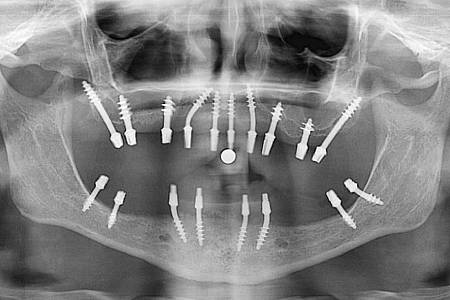

Имплантация базального типа означает хирургическую установку имплантатов прямо в базальный слой костной ткани, что исключает необходимость предварительного увеличения объема кости.

- Введение базальных имплантатов: хирургическое вмешательство для установки имплантов в кость.